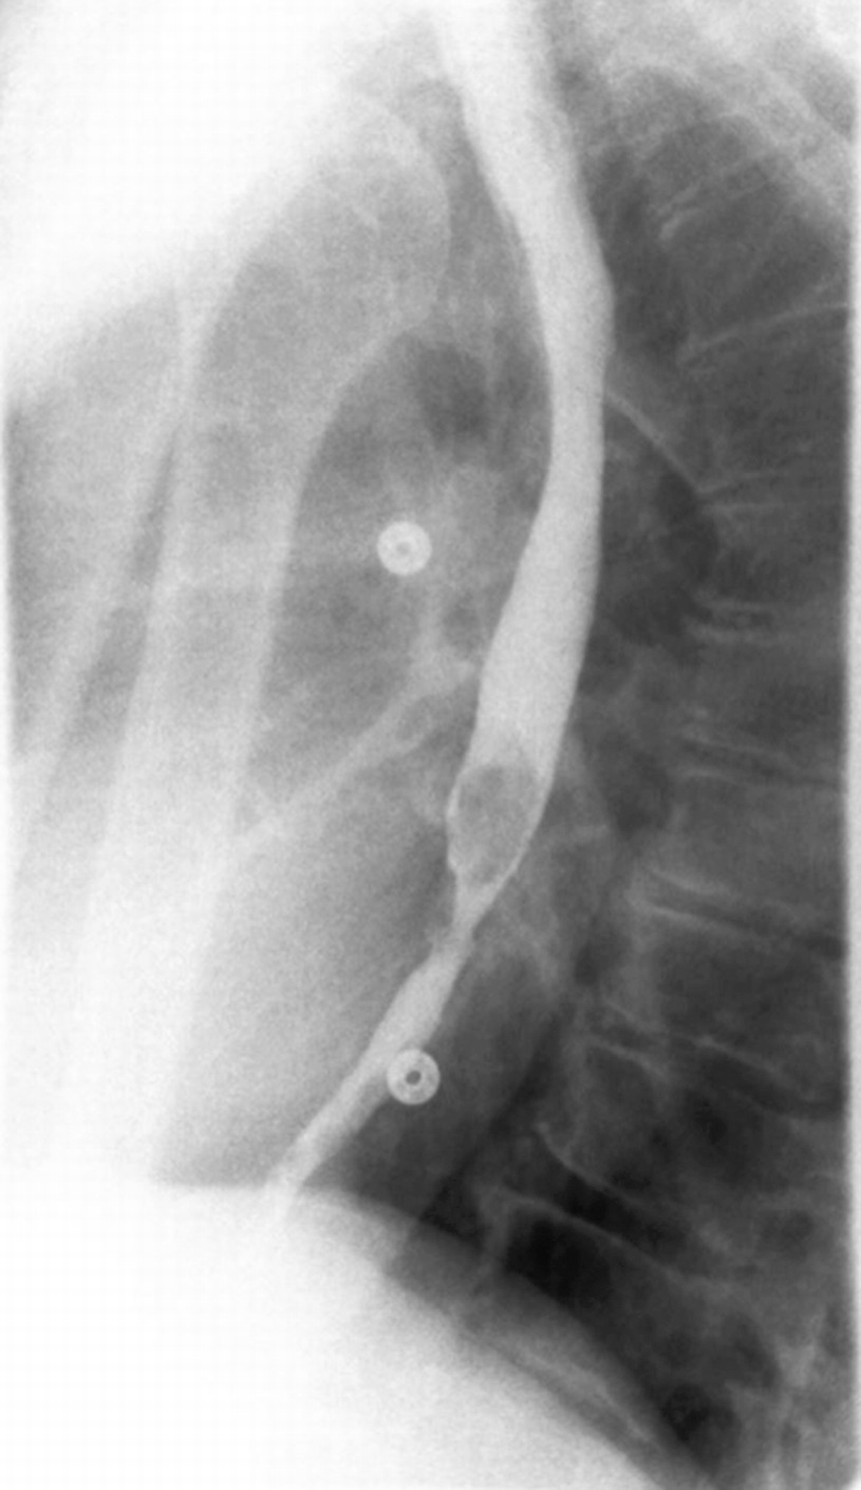

Barium Esophagogram In Various Esophageal Diseases A Pictorial Essay Debi U Sharma M Singh L Sinha A Indian J Radiol Imaging

Barium Esophagogram In Various Esophageal Diseases A Pictorial Essay Debi U Sharma M Singh L Sinha A Indian J Radiol Imaging from www.ijri.org

However, in barrett's esophagus, columnar epithelium extends to varying degree up into the esophageal body. People who have had gastroesophageal reflux (gerd) for a long time often develop barrett's esophagus. Formulary drug information for this topic. Barrett's esophagus is associated with an increased risk of developing esophageal cancer. Barrett's oesophagus is a condition which affects the lower gullet (oesophagus). As well as symptoms, treatments, complications, diet, and home care. You may get barrett's esophagus if you have frequent heartburn that lasts for many years. Figure 2 illustrates the difference between squamous and columnar epithelium. Although the risk of developing esophageal cancer is small, it's important to have regular checkups with careful imaging and extensive biopsies of the esophagus to check for precancerous cells (dysplasia). Barrett's esophagus is associated with an increased risk of developing esophageal cancer. Although esophageal cancer (ec) is the eighth most common cancer in several european countries, it is one of deadliest worldwide. Its importance lies in its predisposition to evolve into esophageal cancer. So doctors recommend that people over the age of 50 with chronic gerd symptoms get screened with endoscopy, especially if they are white, overweight, and male. Barrett's metaplasia (or barrett's oesophagus, as it is sometimes called) is the clinical situation in which intestinal cells are found in the tissue of the lower end of the oesophagus.71 in the strictest terms, it is the conversion of stratified squamous epithelium to columnar epithelium and is. Endoscopy is done in a doctor's office while under. Barrett's esophagus does not usually. Barrett's oesophagus refers to metaplasia of the oesophageal epithelial lining, whereby normal stratified squamous epithelium is replaced by simple columnar epithelium. It's more common in people with acid reflux (gerd), but can develop without having gerd. Analysis of radiographic signs in 29 cas. Management ranges from monitoring your esophageal lining with endoscopies to treatments to remove damaged tissue. Barrett's esophagus is a complication of chronic gastroesophageal reflux disease (gerd). Barrett's esophagus is the condition in which a metaplastic columnar epithelium that has both gastric and intestinal features replaces the stratified squamous e. Heartburn is also called gerd (gastroesophageal reflux disease) or acid reflux. Although anyone can develop it, those at higher risk are men, caucasians, hispanics and senior citizens. People with barrett's esophagus may develop a rare cancer called esophageal adenocarcinoma. Hiatal hernia reflux esophagitis columnar epithelium barrett esophagus reticular pattern. Although the risk of developing esophageal cancer is small, it's important to have regular checkups with careful imaging and extensive biopsies of the esophagus to check for precancerous cells (dysplasia). It is named after the doctor who first described it. Barrett's esophagus is a rare, irreversible condition characterized by changes in the internal lining of the esophagus (food pipe). Overview of barrett's esophagus including the causes; Barrett's esophagus is when the normal cells that line your food pipe (esophagus) turn into cells not usually found in your body.